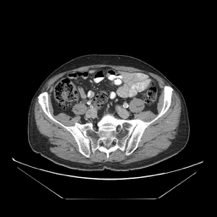

4. RIFE를 이용한 Image Interpolation(CT 이미지)

http://www.castlemountain.dk/atlas/index.php?page=mulrecon에서 다운로드 하였습니다.(JPEG파일)

http://castlemountain.dk/mulrecon/abdomenBladderCancerCT.zip : 다운로드 주소

입력 이미지로 다음의 이미지를 삽입하였습니다.

출력 결과 위의 두 이미지 사이에 밑의 3이미지가 추가로 생성되었습니다.